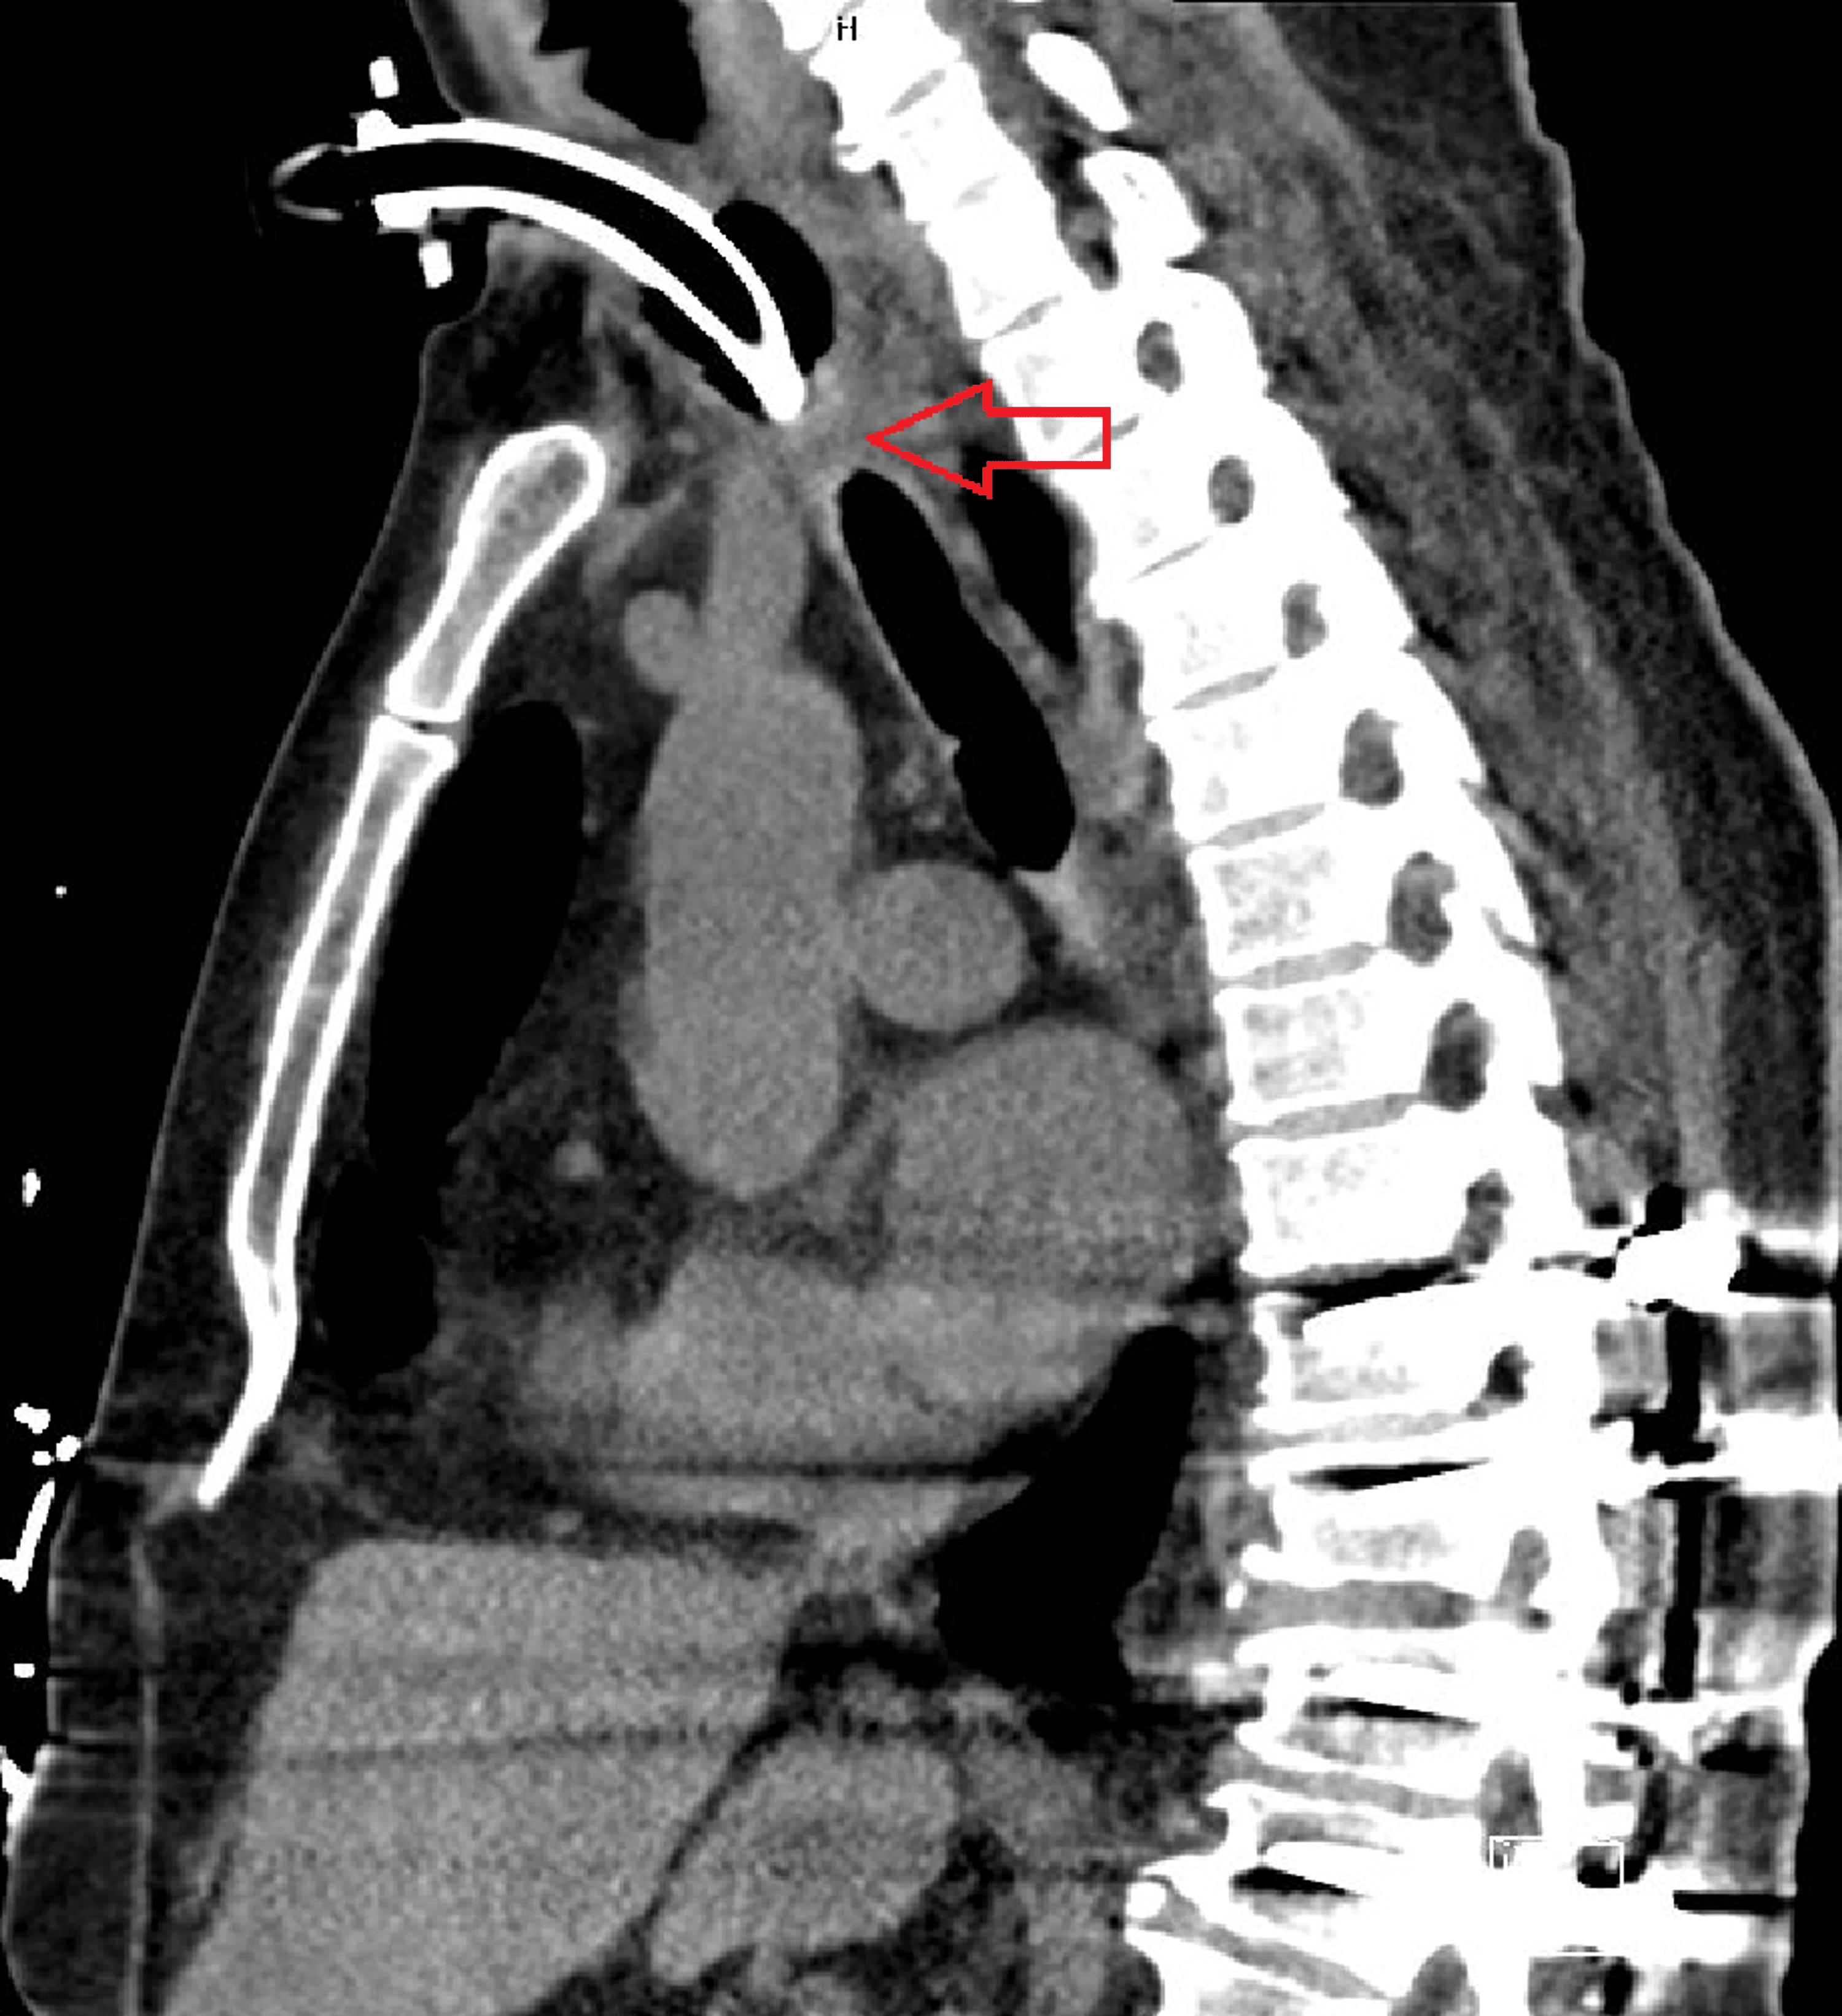

Tracheal Stenosis due to Prior Tracheostomy Chest Case Studies Tracheal Stenosis Due To Tracheostomy Tracheal stenosis is a possible indication for tracheostomy if the airway is obstructed, resulting in difficulty breathing. Tracheal stenosis happens when you have inflammation or scar tissue in your trachea that makes your trachea narrower and makes it more. Severe tracheal stenosis resulted in. Tracheal stenosis is the most common late airway complication of tracheostomy. Although infraglottic stenosis most commonly. Tracheal Stenosis Due To Tracheostomy.

CT images showing severe tracheal stenosis. A, CT scan showing patent Tracheal Stenosis Due To Tracheostomy Tracheal stenosis happens when you have inflammation or scar tissue in your trachea that makes your trachea narrower and makes it more. Severe tracheal stenosis resulted in. Tracheal stenosis is the most common late airway complication of tracheostomy. Tracheal stenosis is a possible indication for tracheostomy if the airway is obstructed, resulting in difficulty breathing. Although infraglottic stenosis most commonly. Tracheal Stenosis Due To Tracheostomy.

Tracheal Stenosis due to Prior Tracheostomy Chest Case Studies Tracheal Stenosis Due To Tracheostomy Severe tracheal stenosis resulted in. Tracheal stenosis (ts) following a tracheostomy commonly results from excess granulation tissue formation around the tracheal. Although infraglottic stenosis most commonly results from endotracheal tube damage, it may occur after damage of the 1st tracheal ring or cricoid. Tracheal stenosis is the most common late airway complication of tracheostomy. Tracheal stenosis is a possible indication. Tracheal Stenosis Due To Tracheostomy.

Tracheal Stenosis due to Prior Tracheostomy Chest Case Studies Tracheal Stenosis Due To Tracheostomy Severe tracheal stenosis resulted in. Although infraglottic stenosis most commonly results from endotracheal tube damage, it may occur after damage of the 1st tracheal ring or cricoid. Tracheal stenosis happens when you have inflammation or scar tissue in your trachea that makes your trachea narrower and makes it more. Tracheal stenosis (ts) following a tracheostomy commonly results from excess granulation. Tracheal Stenosis Due To Tracheostomy.

Tracheal Stenosis due to Prior Tracheostomy Chest Case Studies Tracheal Stenosis Due To Tracheostomy Tracheal stenosis is a possible indication for tracheostomy if the airway is obstructed, resulting in difficulty breathing. Although infraglottic stenosis most commonly results from endotracheal tube damage, it may occur after damage of the 1st tracheal ring or cricoid. Severe tracheal stenosis resulted in. Tracheal stenosis is the most common late airway complication of tracheostomy. Tracheal stenosis (ts) following a. Tracheal Stenosis Due To Tracheostomy.